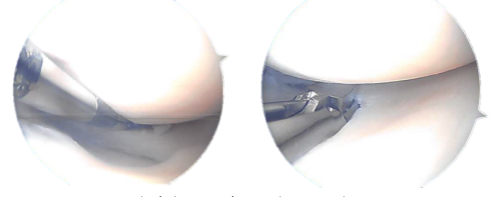

The knee was completely irrigated and shed. The knee was closed with nylon #3-0 sutures. Dry treatment was done with Adaptic, 4 x 4, and Webril. TED hose was used on the thighs. The ligature was taken off. The patient was successfully extubated.

Final pictures taken during operation